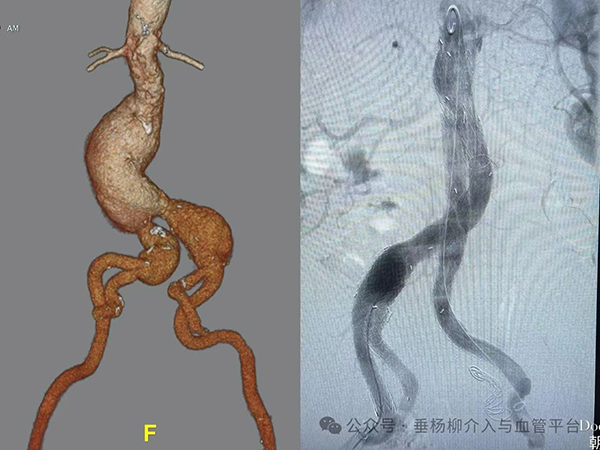

患者男性,73岁,体检发现主髂动脉巨大动脉瘤收入院。患者既往冠心病、房颤,以及高血压病史多年,冠脉支架植入术后3年,规律口服药物治疗。入院后进一步检查,腹主动脉肾下瘤样样张直径达5.2cm;右髂总动脉瘤样扩张直径达4.1cm,左髂总动脉瘤样扩张直径达3.2cm。面对如此复杂的病例,血管外科团队没有退缩。迅速召集全科医生进行讨论。髂内动脉,这条鲜为人知的“生命隐秘通道”,不仅滋养着人体的盆腔器官,更是臀肌活力的源泉,一旦受损,后果不堪设想。因此临床治疗时保留一侧髂内动脉至关重要。本例患者如何隔绝双侧巨大髂总动脉瘤,同时保留一侧的髂内动脉是本次治疗的难点。传统开放手术不仅创伤大、恢复慢,且并发症风险高。腔内介入技术可以通过覆膜支架隔绝主髂动脉瘤瘤体,防止瘤体进一步扩张和破裂,同时对一侧髂内动脉进行重建,确保盆腔血液供应不受影响。

充分准备后,手术在麻醉师和导管室团队的紧密配合下顺利进行。穿刺股动脉建立入路,栓塞左侧髂内动脉,置入右侧髂动脉分支支架IBE重建髂内动脉,置入腹主动脉主体支架及分支支架,整个手术有条不紊的进行,成功克服血管重度扭曲难关,经过2小时手术顺利结束。

术后,患者在血管外科医护团队的精心护理下,恢复情况良好。血压控制稳定,未出现任何并发症。复查结果显示,动脉瘤得到有效的隔绝,没有内漏,右侧髂内动脉血流通畅,臀部和下肢功能未受影响。患者及家属对对医护团队的专业技术和人文关怀给予了高度评价。